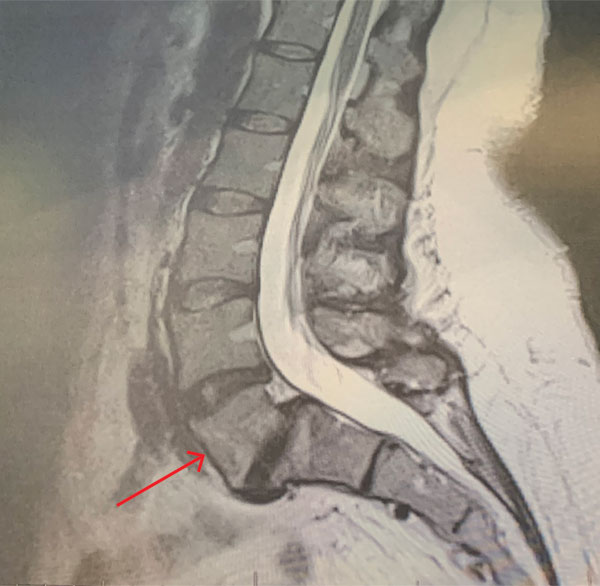

MRI of the lumbar spine (Fig. 1) demonstrated a grade 1-2 spondylolisthesis at L5-S1 with bilateral pars defects with significant L5-S1 foraminal compression. She had an associated L4-5 retrolisthesis with secondary degenerative changes with a dysmorphic trapezoidal L5 vertebral body.

Figure 1: Sagittal MRI T2-Weighted image of lumbar spine demonstrating grade 1 L5-S1 spondylolisthesis and retrolisthesis of L4-5 with significant degenerative disease of both segments. Note dysmorphic L5 vertebral body (arrow).